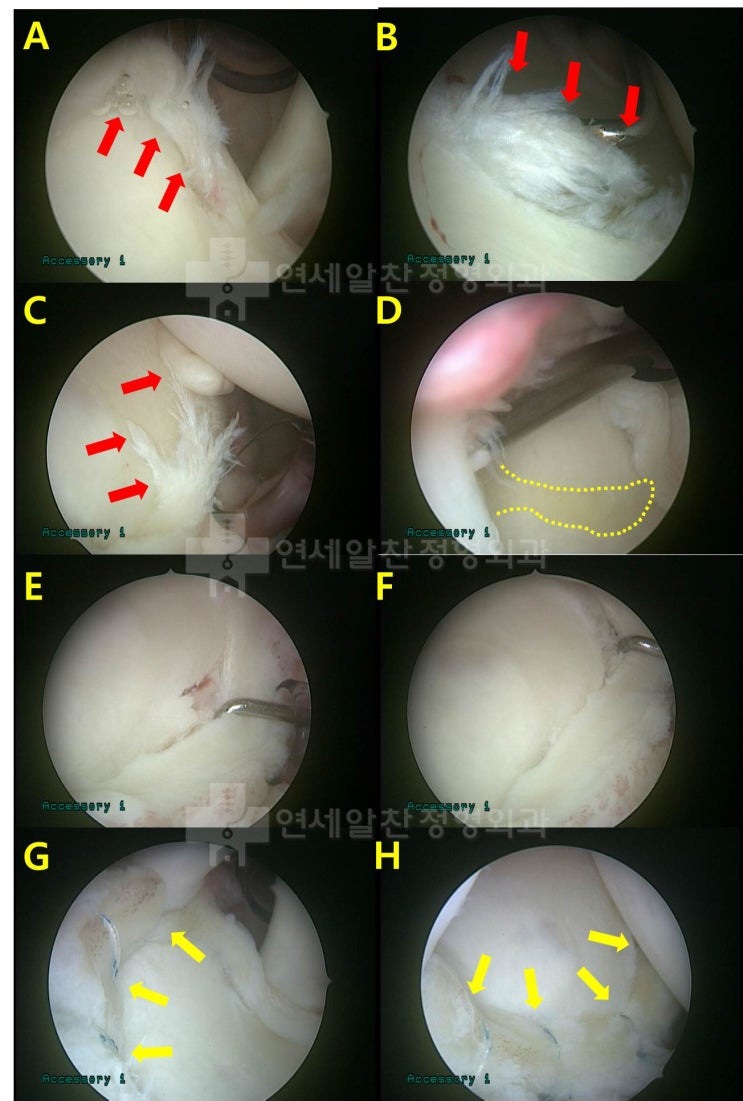

완전히 복원되지 않는 광범위 회전근개 파열 :  인조인대를 이용한 회전근개 봉합술 및 보강술 결과

오늘은 회전근개 파열이 되고 너무 오래 되어서 완전히 해부학적으로 복원되지 않는 경우 인조인대(allomen...